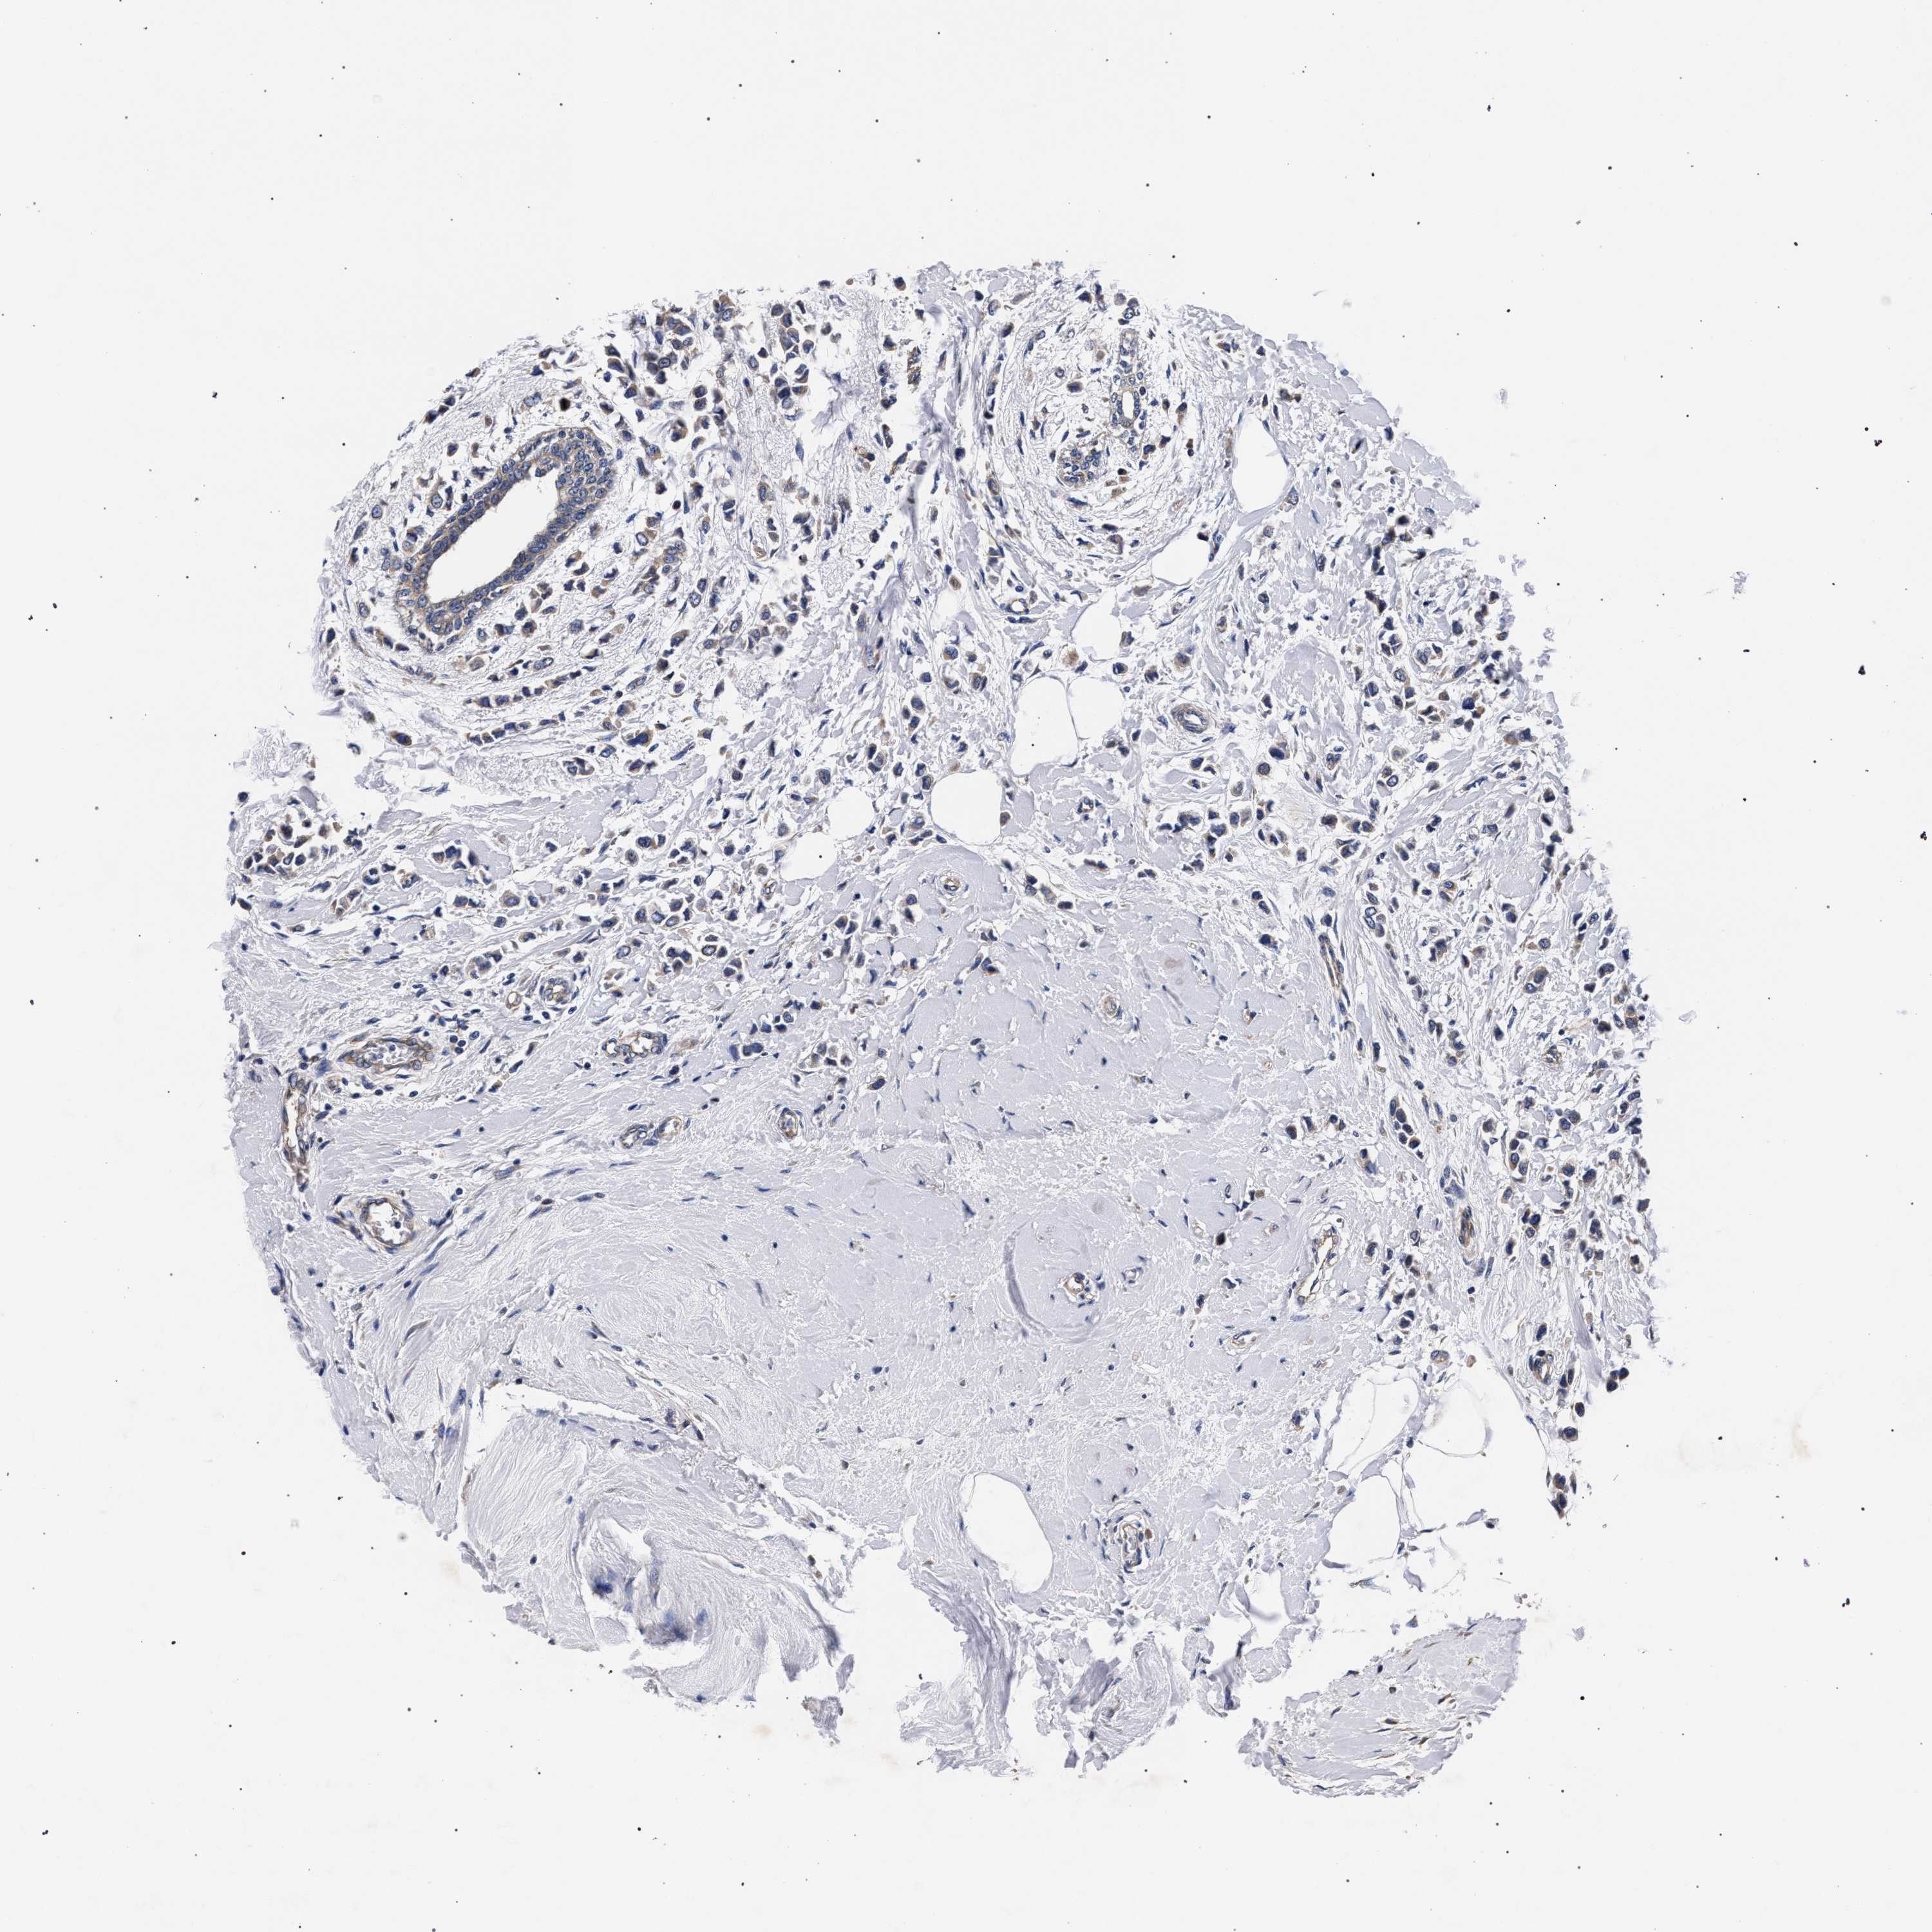

CANCER BREAST CANCER Show tissue menu

BRCA TCGA BRCA VALIDATION PROTEIN EXPRESSION

ANTIBODIES

AND

VALIDATION